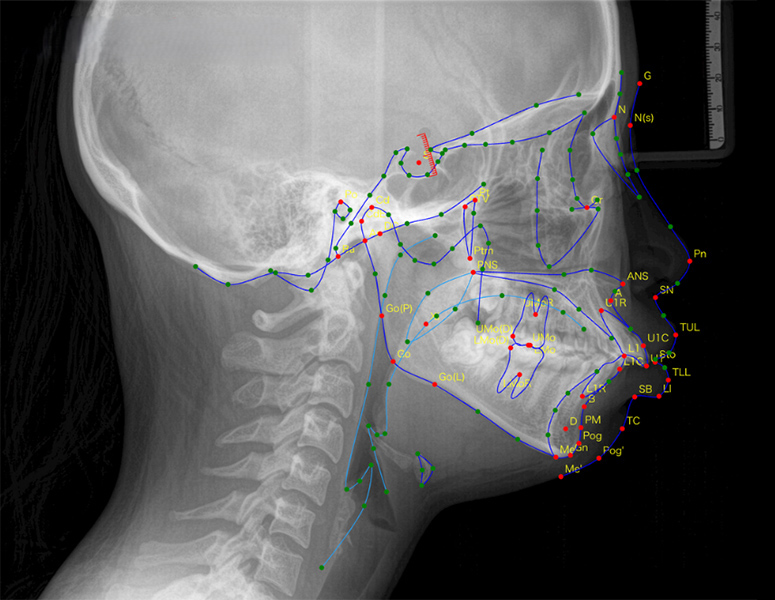

矯正治療における「セファロ分析」とは、セファログラム(側面頭部エックス線規格写真)と呼ばれる特殊なレントゲン写真をもとに、顔面の骨格や歯の位置関係を数値的に分析する手法です。

セファログラムは、一定の条件(距離・角度)で撮影される規格化されたレントゲン写真です。この写真を分析することで、以下のような情報を得ることができます。

・上あごと下あごの大きさや前後的な位置関係

・上下の前歯の傾斜角度

・顔面の成長パターンや骨格的な特徴

・歯と唇・軟組織のバランス

・気道の形態

これらの情報は、矯正治療の方針を決定する上で非常に重要です。たとえば、出っ歯(上顎前突)の方の場合、その原因が「上あごの骨が前に出ている」のか、「下あごの骨が後ろに引っ込んでいる」のか、あるいは「上の前歯が前に傾いているだけ」なのかによって、治療のアプローチはまったく異なります。

セファロ分析は、こうした見た目だけではわからない骨格的な問題を客観的な数値で把握するための、矯正治療における「設計図」ともいえる技術なのです。